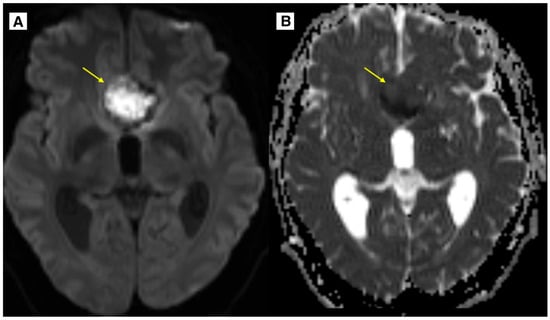

2.2. Imaging Findings